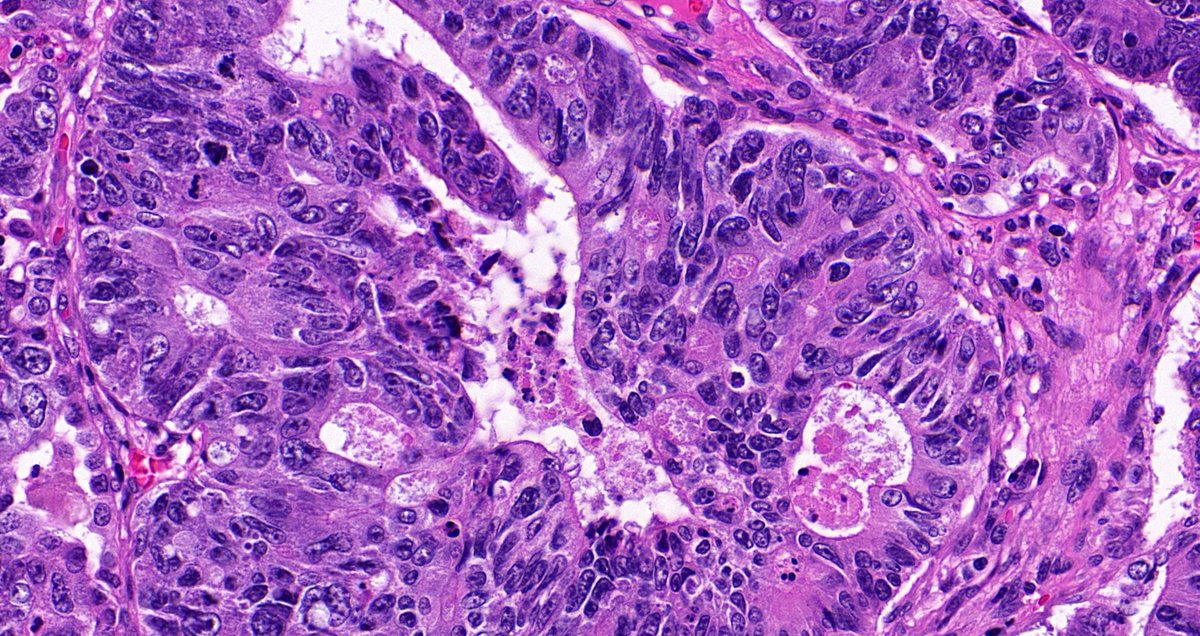

Remember that rare cytoplasmic-only p53 staining pattern?  Here’s a great example of it in a high-grade serous carcinoma!  Important to recognize as abnormal: this is NOT wild-type and indicates a TP53 mutation!